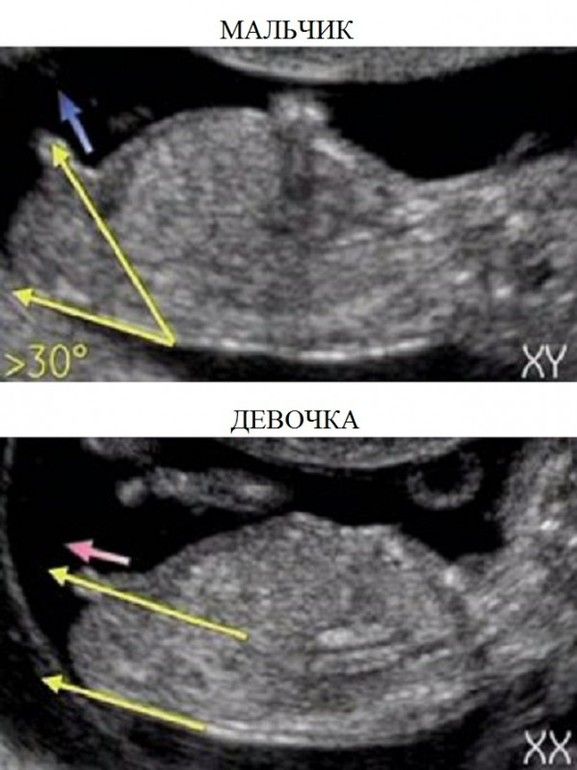

Изображение

Это сагиттальный срез, по нему нельзя рассмотреть пол ), зато хорошо виден сам эмбрион